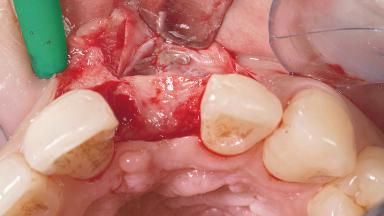

Late Placement of an Implant in a Maxillary Left Central Incisor Site

A 30-year-old female patient had lost tooth 21 and was referred to our clinic for consultation and treatment. Due to advanced apical infection, tooth 21 had been extracted two months earlier at another clinic and an acrylic-resin tooth had been bonded to the adjacent teeth. The patient desired implant treatment to avoid any damage to the adjacent natural teeth. While the patient had no history of any systemic disorder, she was a heavy smoker and exhibited medium to advanced periodontitis in the entire jaw. After the initial treatment to achieve a pocket probing depth of less than 4 mm and no bleeding on probing, a decrease in the height of the papillae mesial and distal to the extraction site and overall gingival recession were observed.

Bone Augmentation Horizontal|Staged

Augmentation Materials Autogenous chips|Membrane

Bone Volume Deficient horizontally, requiring prior grafting